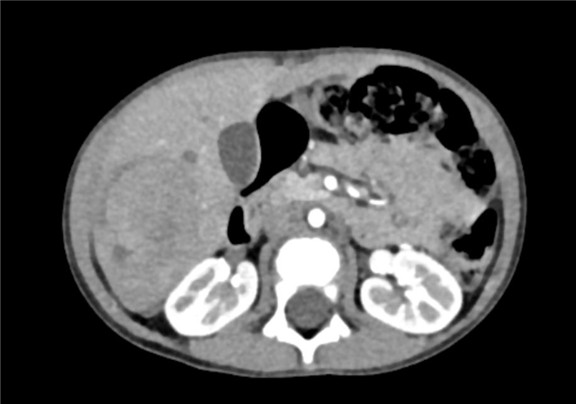

下腹部增强CT示:肝右叶较大肿块影,考虑恶性肿瘤(肝母细胞瘤)可能性大,较前减小

术前CT检查:

动脉期

静脉期